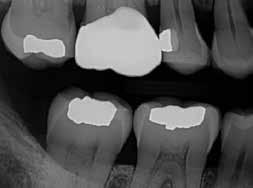

MarchApril 2026 ISSUU by Florida Dental Association - Issuu